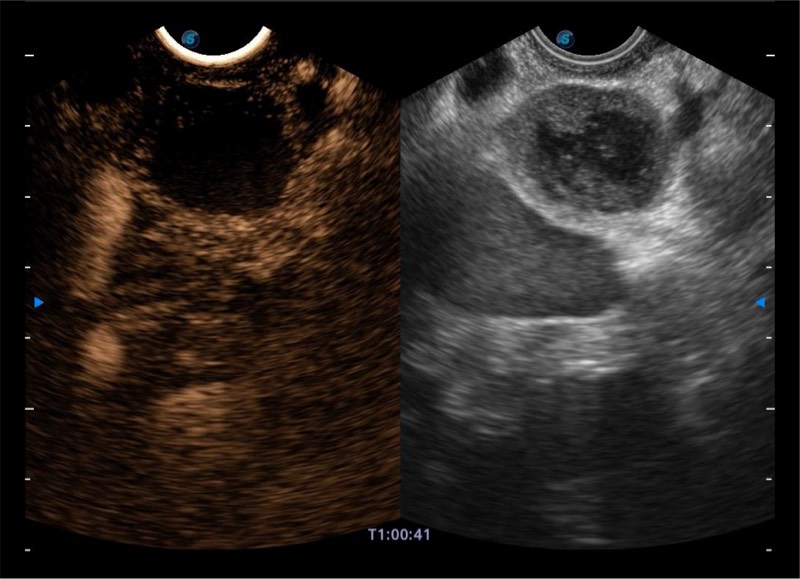

搭载百万级CMOS成像技术

及自主研发凸阵换能器,

可呈现优质的内镜和超声画面

基于二十年的超声技术积累,玖鼎集团提供了最新一代的独立超声主机,在提供高质量图像的同时满足多学科使用。具备常见多普勒技术并提供弹性成像、声学造影等高端影像技术。新一代传感器具有更强的抗干扰能力并减少图像伪影。

4-12MHZ宽频输出